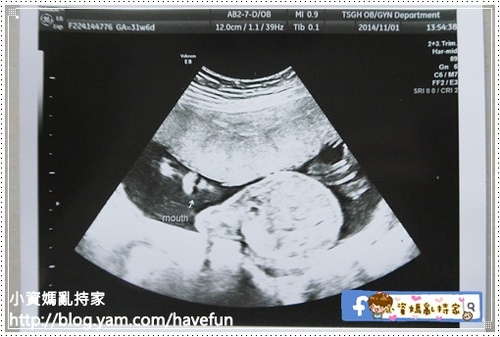

另外醫生發現有2個沒看到(性別跟嘴唇)

直接叫我到隔壁高層次超音波室幫我看

就這樣我又幸運得多拿到兩張拉拉的特寫,嘴唇跟~~~屁股XD

最後因為位置關係,嘴唇沒有照到,超音波師說沒關係可以下次再照

Lip: